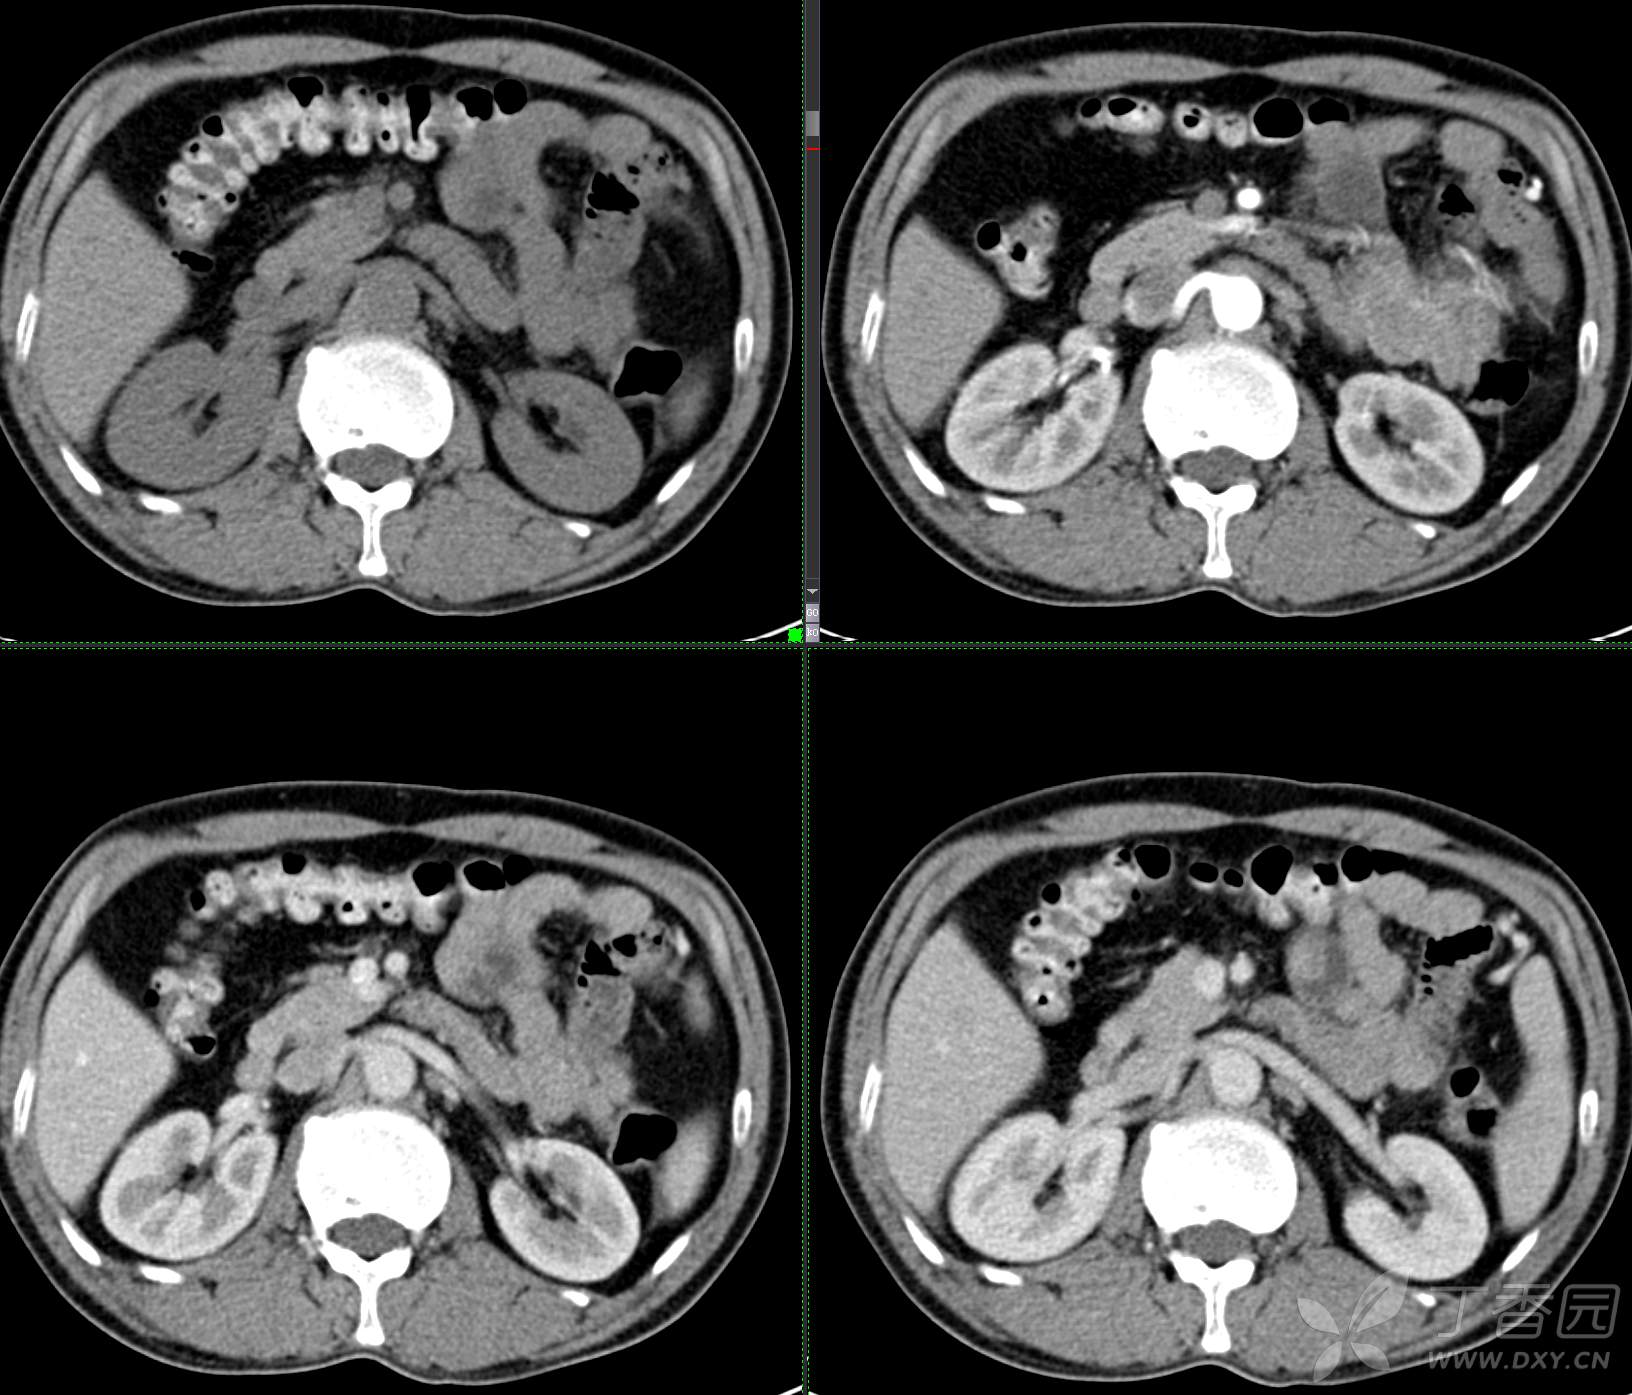

讨论:小肠病变,间质瘤?淋巴瘤?小肠腺癌?